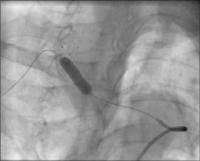

Stenose - Arbeitsprojektion

Abbildung 2: 3-D-Rekonstruktion der Stenose zur Festlegung der besten Arbeitsprojektion.